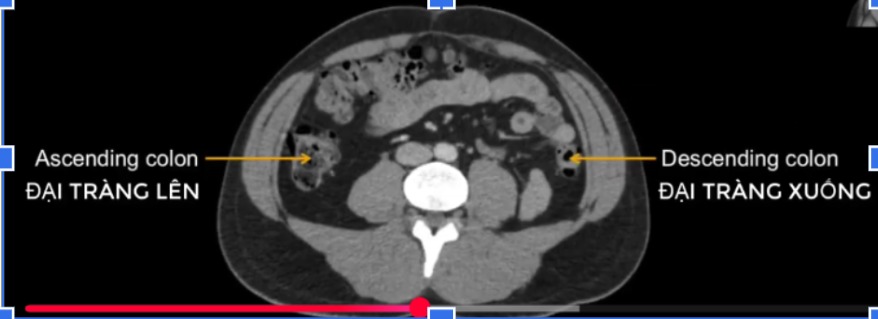

cơ chéo ngoài? trong? ngang b?

cq trong hình ?